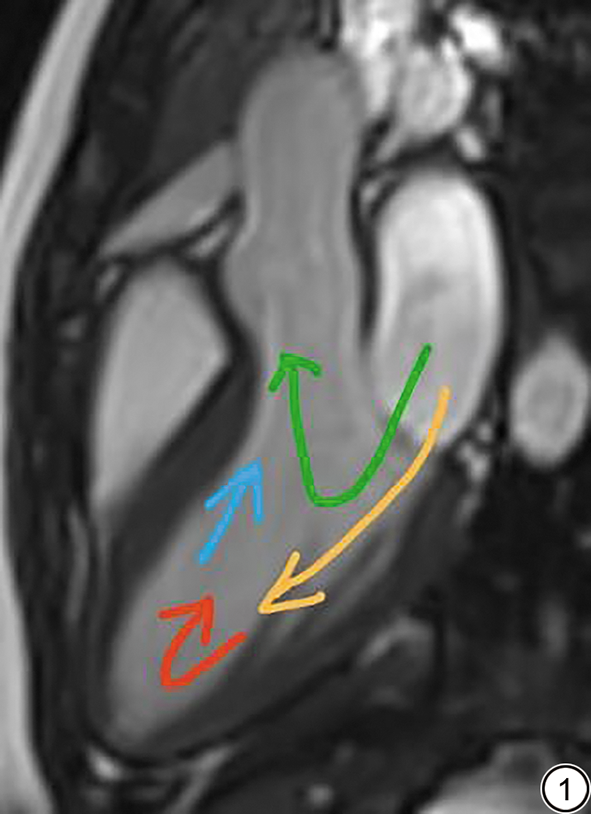

对照组和PVCs组左心室血流可视化结果见表3图2图3。血流成分方面,PVCs组直接血流低于对照组(P=0.045)。与PVCs-M组相比,PVCs-S组剩余容积增加(P=0.016),直接血流减少(P=0.049)。

图2  对照组儿童左室血流的可视化(男,12岁,健康儿童)。2A、2C:舒张期左室血流分量的路径线可视化。2B、2D:收缩期左室血流分量可视化。直接血流为绿色,占比44.41%;保留流入量为黄色,占比20.41%;延迟射血为蓝色,占比22.6%;剩余容积为红色,占比12.57%。

Fig. 2  Visualization of left ventricular blood flow in children of the control group (male,12years, a healthy child). 2A and 2C show the pathline visualization of left ventricular blood flow components during diastole; 2B and 2D show the visualization of left ventricular blood flow components during systole. Direct flow is green, accounting for 44.41%; retained inflow is yellow, accounting for 20.41%; delayed ejection flow is blue, accounting for 22.6%; residual volume is red, accounting for 12.57%.